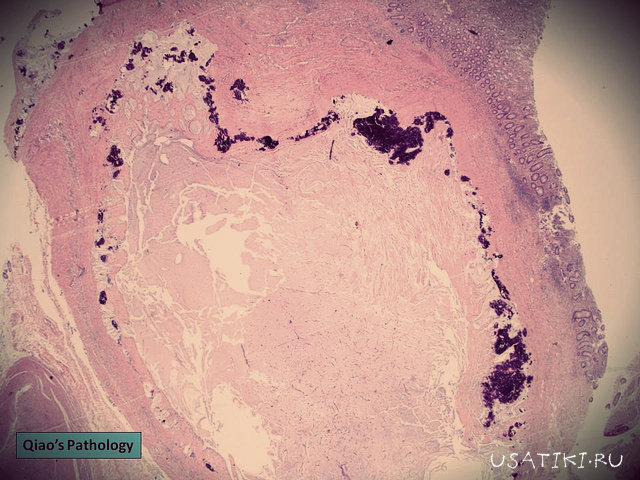

Seul un vétérinaire peut déterminer si un animal de compagnie est atteint d'un cancer ou d'une tumeur bénigne sans gravité après de nombreux examens complémentaires (dont une biopsie). Une échographie peut aider à localiser précisément la tumeur. tumeurL’examen radiologique permet de déterminer si des vaisseaux sanguins importants sont comprimés, la taille et la consistance de la tumeur, ainsi que d’autres détails mineurs. Les rayons X offrent une vue quasi complète de l’animal et permettent de détecter la présence ou l’absence de métastases, fréquentes en cas de cancer. L’histologie et la cytologie examinent les tissus et les cellules, permettant ainsi de déterminer si l’animal est atteint de cancer.